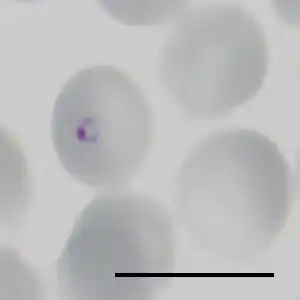

| Ringstadium van Plasmodium falciparum in een geïnfecteerde erytrocyt. Het zwarte streepje is 10 μm lang. | ||||||||||||